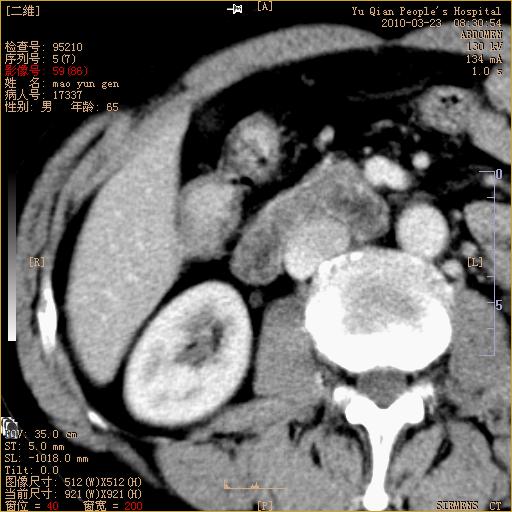

标题: CT25266:消瘦月余,前来肝部检查,请看看肠腔 [打印本页]

标题: CT25266:消瘦月余,前来肝部检查,请看看肠腔

升结肠肠壁增厚,不均强化,考虑升结肠腺癌可能性,建议肠镜检查。

1)考虑升结肠癌。2)右肾小囊肿。